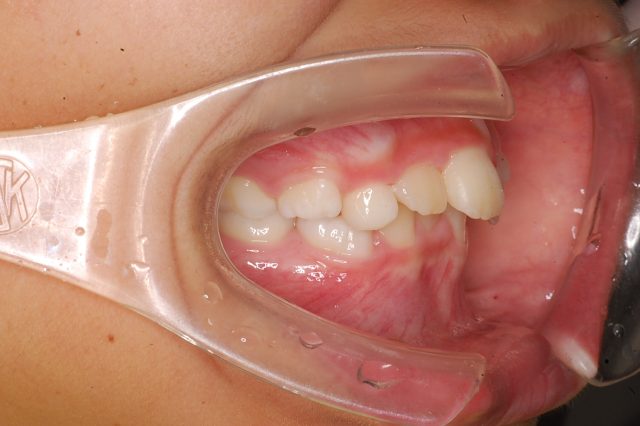

8歳男の子インビザラインファースト:永久歯スペース不足を解消

| 年齢・性別・主訴 | 8歳男の子 永久歯が並ぶスペースが足りない |

他のBefore